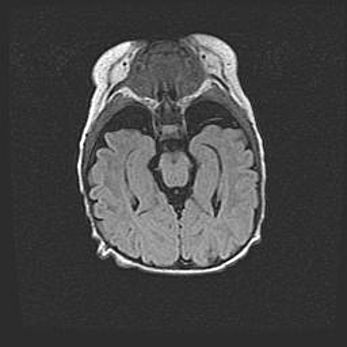

Мальформация Денди-Уокера. Киста задней черепной ямки.

Агенезия мозолистого тела.

Возраст: 2,5 месяца

Вес: 2420 г

Пол: женский

Окружность головы: 37 см

Срок гестации: 32 недели

Мальформация Денди—Уокера — редкий вид патологии ЦНС, представляющий собой врожденный порок развития каудального отдела ствола и червя мозжечка, ведущий к неполному раскрытию срединной (Мажанди) и латеральных (Лушка) апертур IV желудочка мозга. Для этогно синдрома характерна триада симптомов: гипотрофия червя мозжечка и/или полушарий мозжечка, кисты задней черепной ямки, гидроцефалия различной степени. В 70% случаев порок сочетается и с другими аномалиями головного мозга, в частности с агенезией мозолистого тела.